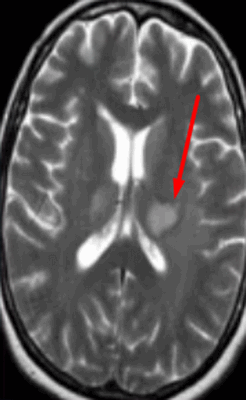

Картина развития ишемического инсульта на МРТ (Т1- и Т2-взвешенные изображения)

Острый период (1-7 день) характеризуется появлением четко ограниченных светлых участков на МРТ в Т2-взвешенном режиме. На Т1 ВИ очаги некроза имеют гипоинтенсивный сигнал.

Головной мозг на МРТ при разных режимах сканирования

Для заболевания характерно появление очагов некроза, вызванного нарушением кровоснабжения определенного участка мозга. В острой стадии наблюдается утолщение извилин коры головного мозга, стирается граница между серым и белым веществом. В период восстановления зону инфаркта определяют как участок кистозного или глиозного перерождения.

Для лакунарного инсульта, представляющего разновидность ишемии, характерно появление небольших (до 20 мм) очагов и кровоизлияний в области глубинных структур головного мозга. Причиной служит тромбоз мелкой внутричерепной артерии, вызвавший образование кисты (лакуны).